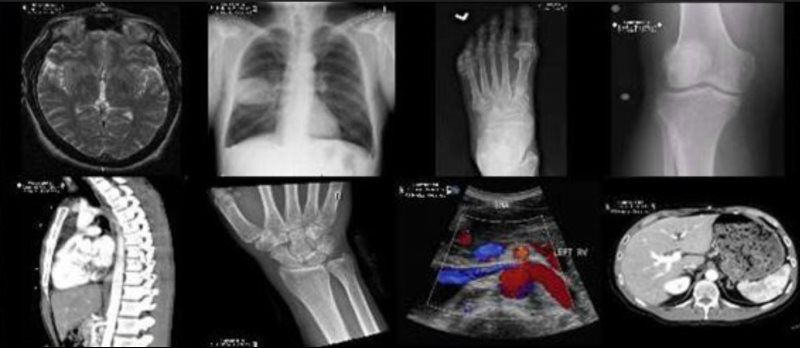

What We Interpret

RWBarnett Radiology, LLC offers a broad range of image interpretation, from the most complex cases to the simplest, most straight-forward. With attention to detail, we provide results that allow ordering physicians and surgeons to take next steps in caring for their patients without the need for additional clarification and direction. For more details, choose "What We Interpret" here: